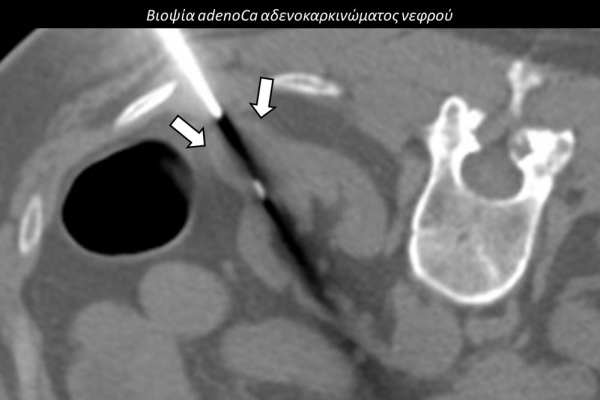

Η διαδερμική βιοψία είναι μία ελάχιστα επεμβατική μέθοδος λήψης υλικού από τον όγκο για κυτταρολογική και ιστολογική εξέταση, από εστιακές αλλοιώσεις του ήπατος, πνεύμονα, νεφρού κλπ. Συστήνεται από τον κλινικό ιατρό ανάλογα με το είδος και το μέγεθος της βλάβης και πραγματοποιείται με ασφάλεια από επεμβατικό ακτινολόγο με την καθοδήγηση αξονικού τομογράφου ή υπερήχων. Στη σύγχρονη ογκολογική θεραπεία όπου γίνεται προσπάθεια καταπολέμησης του καρκίνου σε μοριακό επίπεδο κρίνεται αναγκαία η ακριβής ιστολογική ταυτοποίηση του όγκου ώστε να εφαρμοσθεί εξατομικευμένη θεραπεία για το βέλτιστο αποτέλεσμα. Οι κατευθυνόμενες βιοψίες στοχευουν στο να παρέχουν στον κλινικό ογκολόγο το απαραίτο ιστοπαθολογικό υλικό που θα του επιτρέψει να εφαρμόσει την κατάλληλη θεραπεία για τον ογκολογικό ασθενή.